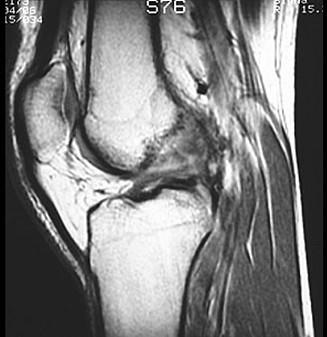

问题 男,37岁,右膝关节曾有外伤史,现感右膝关节部疼痛,请结合所提供的图像,选择最佳选项 ( )

选项 A、半月板损伤 B、后十字韧带撕裂 C、前十字韧带撕裂 D、胫骨骨折 E、未见异常

答案 C